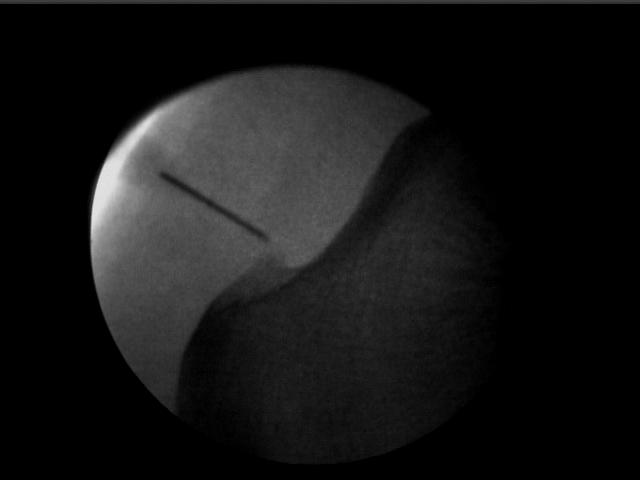

- Espolón Calcáneo

- Infiltración en zona espolón